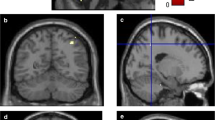

The whole brain voxel-wise regression analysis between FDG-metabolism and SCD-S score is presented in Table 3 and visualized in Fig. 1. Patients with higher SCD-S scores showed decreased metabolism in the following regions: right angular gyrus (p = 0.002, ke = 1223), bilateral middle temporal gyrus (left: p = 0.026, ke = 570; right: p = 0.009, ke = 841), bilateral occipital regions including right precuneus (p = 0.012, ke = 766), and left calcarine sulcus (p = 0.001, ke = 1594), left middle frontal gyrus (p = 0.044, ke = 448) including the orbital part (p = 0.043, ke = 455). Higher SCD-S scores did not correlate with increased metabolism in any region.

Whole brain voxel-wise regression analysis between FDG uptake and SCD-S score. Red-yellow maps illustrate negative correlation between FDG uptake and SCD-S score indicating hypometabolism in these areas. A 3D render view B 2D axial slices. L, left; P, posterior; R, right. Color bar indicates t values. Slices and 3D display were constructed with MRIcroGL, neurological display